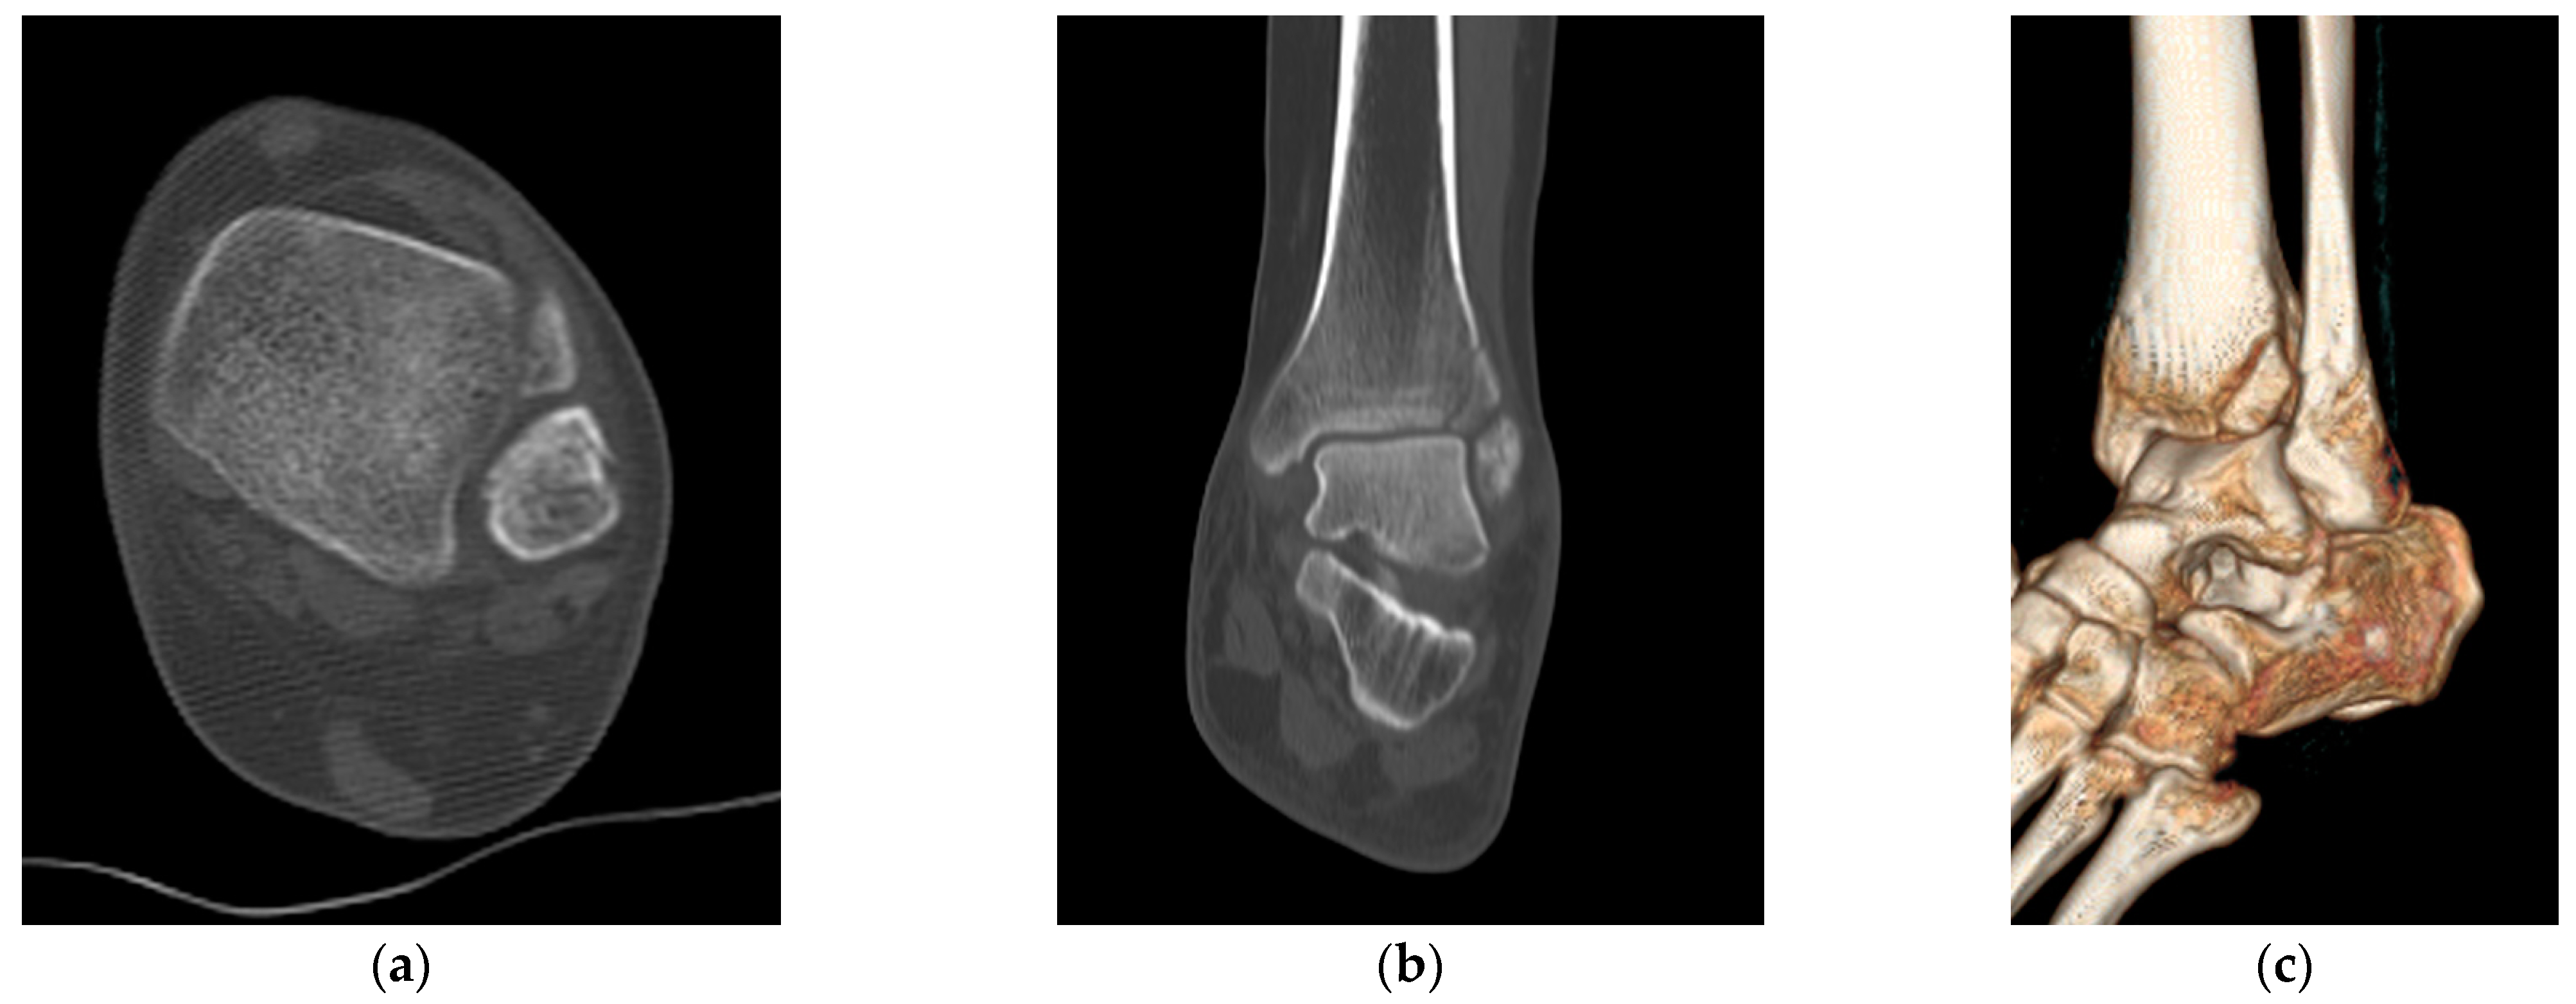

2.3. Radiological Evaluations

- Rammelt, S.; Boszczyk, A. Computed tomography in the diagnosis and treatment of ankle fractures: A critical analysis review. JBJS Rev. 2018, 6, e7. [Google Scholar] [CrossRef]